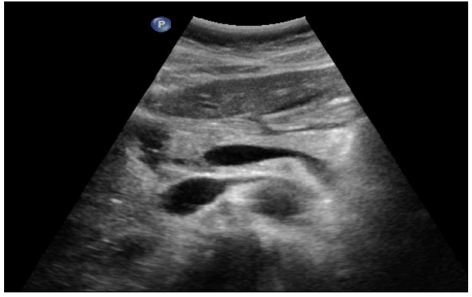

Contraste digestif en radiologie adulte

DANSE E. - UCL

Digestif MASTER 1